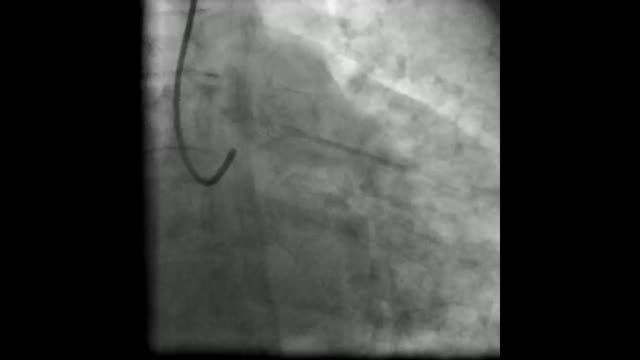

Baseline and follow-up angiographies and intravascular ultrasound.

(A, B) Baseline coronary angiography showed a coronary mass in distal left main coronary artery (white asterisks); Online-Video 1.

(C-D) Baseline intravascular ultrasound showed a large intraluminal mass, presenting a variable gray scale with speckling, suggestive of thrombus.